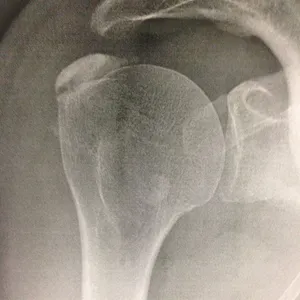

Pour des raisons mal connues (a priori indépendantes du type d’alimentation), des dépôts semblables à de la craie peuvent apparaître au sein des tendons de la coiffe des rotateurs.

- Elles sont responsables d’un conflit sous-acromial : lors de l’élévation du bras, les tendons calcifiés « accrochent » l’arche osseuse de l’acromion, entraînant une douleur aiguë.

- Elles augmentent le risque de rupture tendineuse : proportionnellement à leur taille, elles fragilisent les fibres du tendon.

Ces calcifications sont trop souvent banalisées car elles sont souvent indolores. Malheureusement ces calcifications désorganisent et détruisent à bas bruit les fibres des tendons au sein desquels elles se développent. Laisser grossir ces calcifications augmente le risque de rupture tendineuse lors d’un traumatisme ou d’un effort. Le traitement médical a l’inconvénient de calmer la douleur mais de laisser la calcification grossir à bas bruit. Dès que la taille de la calcification devient conséquente par rapport au tendon, la ponction lavage doit être proposée pour stopper son évolution.